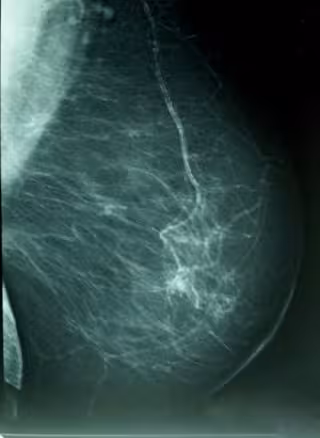

Cáncer De Mama, Densidad Mamográfica

WIKIPEDIA/A. AVENDAÑO